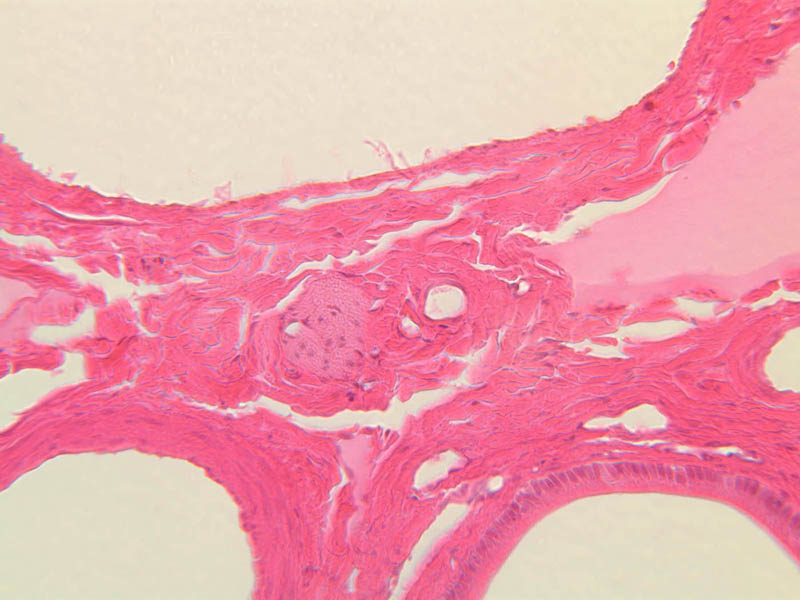

Using the 10X (B-29, B-30)and 40X (B-29) objectives, examine several portal triads, noting the variable number of profiles of hepatic artery, portal vein and bile duct that comprise the portal triad. Near the boundary between adjacent lobules, try to find some of the small elements of the bile duct system known as canals of Hering.

Sections through the wall of the gall bladder appear on slide B-33 (H&E [2.5x, 10x, 20x-labeled, 40x-labeled] [2.5x, 10x, 20x, 40x]). As you examine the epithelium, try to identify the striated border, which functions in absorbing water from the bile. Look for lymphocytes, capillaries and small mucous glands in the lamina propria; lymphocytes often appear to invade the epithelium itself. The gallbladder does not have a discernible submucosa; rather, a muscularis layer, consisting of smooth muscle and connective tissue underlies the mucosa. Some sections may permit identification of both a tunica adventitia, which binds the gallbladder to the liver, and a tunica serosa where the gallbladder faces the peritoneal cavity.